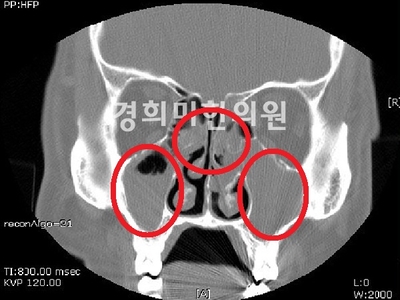

부비강염 CT이미지

편도염 만약 급성 비염의 카타르기가 지나 2차 세균 감염이 되면 끈적끈적한 노란 콧물과 함께 코가 막혀서 후비루가 심해집니다.더 악화되면 부비강염, 중이염, 인두편도염, 기관지염, 폐렴, 장염 등의 합병증이 동반될 수 있습니다.이러한 합병증은 면역력이 저하된 환자나 어린이에게 잘 나타나므로 주의가 필요합니다.